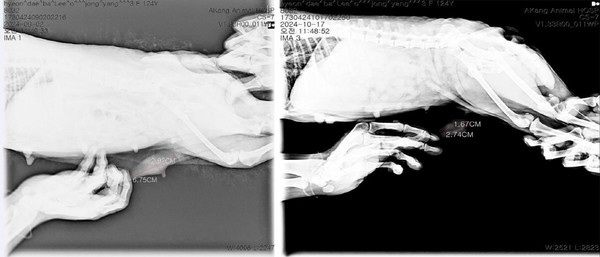

이번 실험에서는 반려견에게 폴리탁셀의 약물 부작용이 나타나지 않는 최대무독성용량(NOAEL) 이하인 4.5㎎/㎏을 회복기 없이 주 1회씩 3회 연속 투여하고 3주 후에 관찰한 결과, 유선종양 크기가 투약 전보다 무려 76.78% 감소했다. 특히 림프절에 전이된 종양 크기는 투약 전보다 74.01%나 줄어들어 폴리탁셀이 전이암 치료효과도 뛰어남을 입증했다.